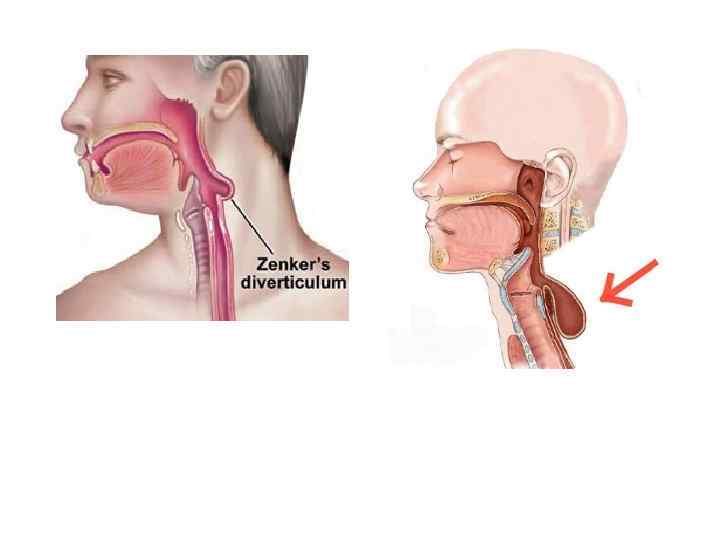

Хирургические доступы к пищеводу • Шейный доступ v Воротникообразный разрез на передней поверхности шеи v Косой разрез Разумовского по переднему краю левой грудиноключично-сосцевидной мышцы • Показания. Удаление инородных тел, глоточнопищеводные дивертикулы, околопищеводные абсцессы и верхнегрудинные медиастиниты.

Хирургические доступы к пищеводу • Шейный доступ v Воротникообразный разрез на передней поверхности шеи v Косой разрез Разумовского по переднему краю левой грудиноключично-сосцевидной мышцы • Показания. Удаление инородных тел, глоточнопищеводные дивертикулы, околопищеводные абсцессы и верхнегрудинные медиастиниты.

• Бифуркационные дивертикулы располагаются на уровне пересечения пищевода с бифуркцией трахеи.

• Бифуркационные дивертикулы располагаются на уровне пересечения пищевода с бифуркцией трахеи.